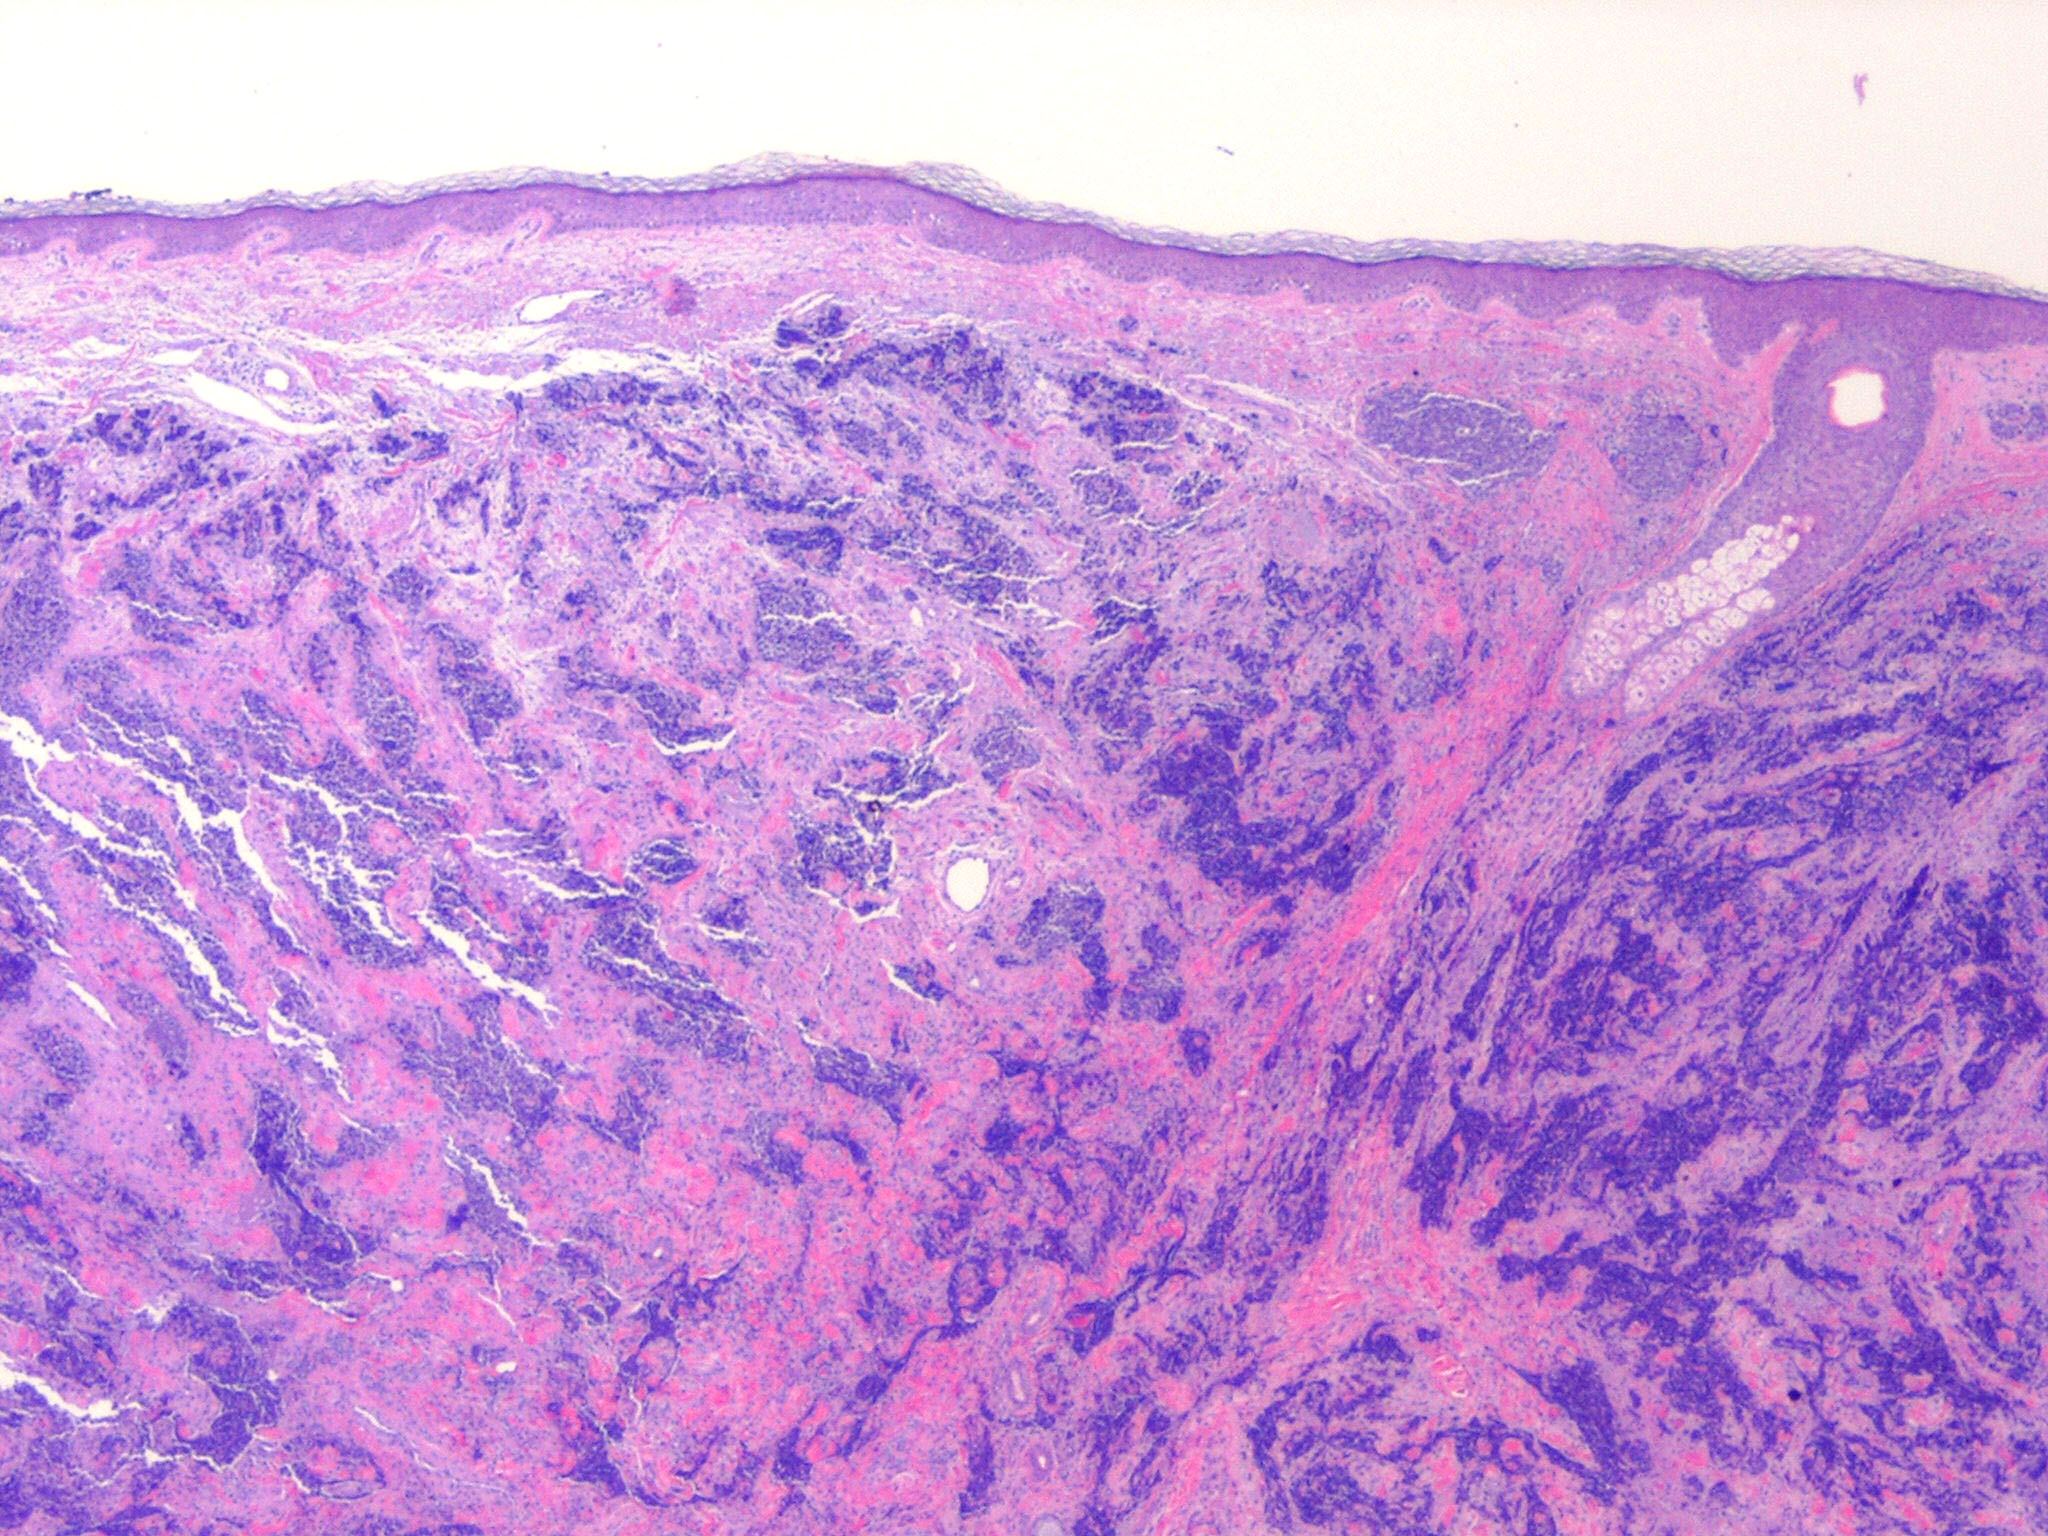

merkel-cell-carcinoma